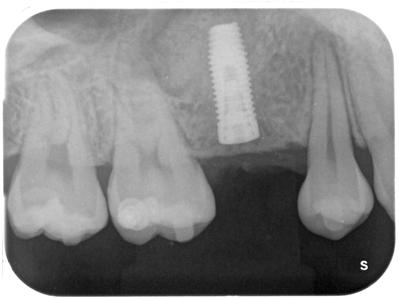

インプラント治療直後。

使用インプラントは、Biomet 3i(アメリカ)

骨移植はソケットリフトで行っている。

インプラント先端周囲に見える白い影が移植された補填材はBioss。

矯正治療中であり、4┘をもう少し遠心移動予定のため、スペースを残してある。